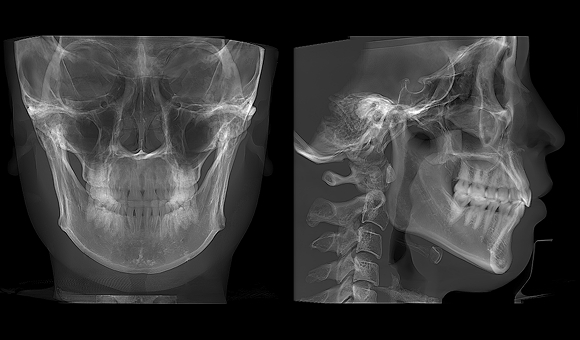

• 3D全景

3D全景

• 3D 正侧位

3D 正侧位